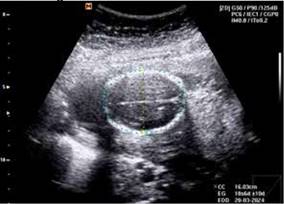

En la valoracion por servicio de medicina materno fetal a las 21.6 semanas de embarazo por FUM (fecha de ultima menstruación) se realiza ecografía obstétrica y doppler de arterias uterinas,con reporte de feto único vivo con situación indiferente, FCF:145 lpm, peso aproximado de 266 g en percentil 1 para Hadlock, líquido amniótico cualitativamente disminuido, con bolsillo vertical máximo de 1.11, placenta corporal anterior grado I de Grannum. DBP: 19.1mm para 19.1 SDG, CC: 160.3 mm para 18.3 SDG, CA: 135.2 mm para 19 SDG, LF: 27.7mm para 18.3 SDG. Tabla 1. Figuras 1, 2.

Tabla 1. Somatometria fetal. Embarazo de 21.6 semanas por amenorrea y 18.6 por ecografía. Percentil 1 de Hadlock.